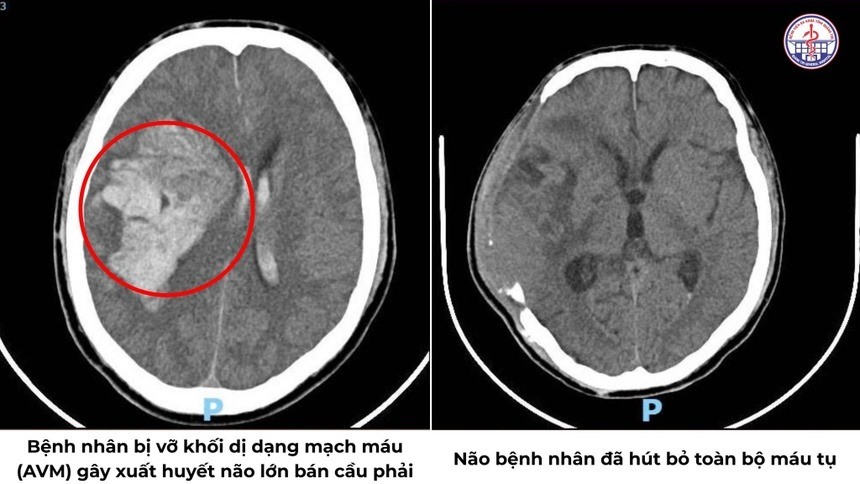

Kết quả chẩn đoán hình ảnh cho thấy tình trạng rất phức tạp: xuất huyết nội sọ lan tỏa nhiều vị trí, có dị dạng thông động - tĩnh mạch (AVM) nội sọ kích thước lớn khoảng 37 x 58 x 87 mm, đồng thời khối máu tụ gây chèn ép nhu mô não.

Trong suốt 3 giờ căng thẳng tại phòng mổ, ê-kíp khoa Ngoại Thần kinh đã đối mặt với một trong những ca phẫu thuật não thách thức nhất. Các bác sĩ tiến hành mở sọ, kiểm soát điểm chảy máu từ dị dạng, hút bỏ máu tụ trong não, giải phóng chèn ép và khôi phục lại tuần hoàn cho vùng não tổn thương.